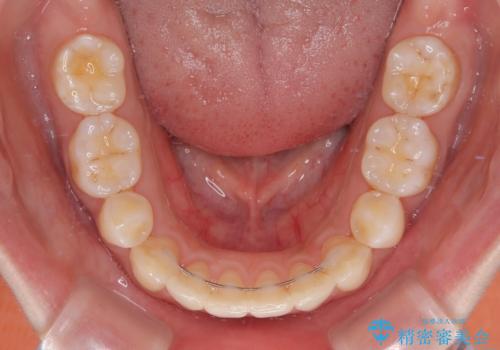

舌の突出癖が原因で後戻りをしたため、舌のトレーニングをしっかりと行っていただき、口元の突出感を改善することができました。

インビザラインの装着時間が守れず、1年強で終わる予定でしたが、4年間を要することとなりました。